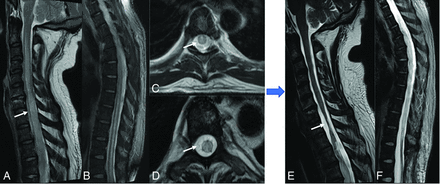

ATM is generally idiopathic or postinfectious immune-mediated demyelination, with EBV being a rare culprit.4,37,38 EBV myelitis is characterized by T2 hyperintensity in the spinal cord that extends over ≥2 segments covering equal or more than two-thirds of the cord, with the thoracic cord being the most affected (Figs 2 and 3). Enhancement patterns range from none to diffuse, with leptomeningeal and nerve root enhancement reported.37,39,40 EBV serologies can aid in diagnosing postinfectious EBV myelitis/ATM because MR imaging findings resemble those of other ATM etiologies. Spinal cord ischemia, MS, neuromyelitis optica, and autoimmune-related myelitis are imaging differential diagnoses for ATM. MS plaques usually affect less than one-half of the cord area and may have concomitant brain lesions. Spinal cord infarction shows bilateral anterior horn cell T2 hyperintensity symmetrically.38 Although rare in immunocompetent individuals, EBV ATM should be considered in cases of high CSF cell count atypical for idiopathic ATM.40

EBV-related transverse myelitis, EBV IgM–positive. T2-weighted sagittal image of the thoracic spine (A) and axial images (B and C) reveal diffuse long-segmental hyperintense signal (arrows) in the spinal cord more in the central gray matter region along with mild cervical cord swelling. No abnormal enhancement on the sagittal T1-weighted postcontrast image (D) was seen.

Presumed EBV myelitis, CSF EBV-positive. Conus biopsy revealed fibrin with macrophages, scant peripheral nerve myelins, and degenerating myelin, most consistent with infection. T2-weighted sagittal image of the cervical (A) and thoracic (B) spine along with axial images (C and D) reveal diffuse long-segmental T2-hyperintense signal in the spinal cord (arrows). Eight-month follow-up sagittal T2 (E and F) images show cord atrophy with persistent signal abnormality (arrow).